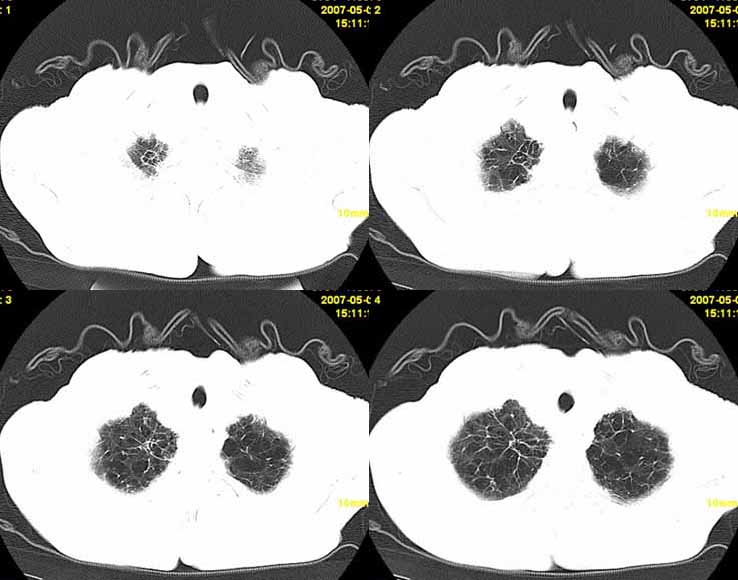

以下是引用小初学者在2007-5-12 11:09:00的发言:[br][br]双肺弥漫性质纤维化(考虑矽肺所致),并发左肺下叶背段周围性肺癌纵隔淋巴转移。

以下是引用zhangzhongshou在2007-5-12 12:09:00的发言:[br]1、左下叶背段周围型肺癌左肺门及纵隔淋巴结转移可能性大。[br]2、弥漫性肺气肿(双侧)。[br]3、双肺间质纤维化。

以下是引用老爱克斯新网客在2007-5-12 12:54:00的发言:[br]1周围型肺癌纵隔肺门淋巴结转移,2肺间质纤维化,